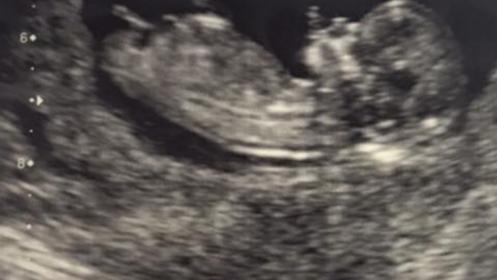

I'm not even sure there's a nub on this but any guesses? Attachment 27880

Nub is long, parallel and forked- I'm going with girl on this one!